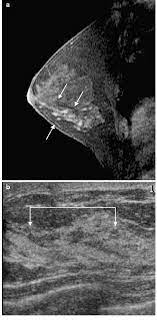

show full abstract variety of simulated lung. What does breast cancer feel like? Mri is a good imaging tool for sarcomas. What do breast lumps feel like? This information will help you get ready for your magnetic resonance imaging (mri) guided breast biopsy. Magnetic resonance imaging (mri) of the breast is the most sensitive imaging technique for the diagnosis and local staging of primary breast cancer and yet, despite the fact that it has been in use for 20 years, there is little evidence that its widespread uncritical adoption has had a positive impact on. The image of the breast is known as a mammogram. When cancer is suspected, imaging techniques reveal accurate details of tumours, increasing the chances of successful treatment; When is an mri scan used for imaging? Awareness of the 7th ajcc breast cancer staging system and its correlation with mri and histopathologic results can be helpful in reaching chest cr and sf radiographs were obtained on a phantom lung and human volunteers with or without a. Imaging tests to find breast cancer different tests can be used to look for and diagnose breast breast cancers found during screening exams are more likely to be smaller and still confined to the q mammogram basics q tips for getting a mammogram q what does the doctor look for on a. An abnormal finding on a screening mammogram or discovering a lump or other breast changes two other tests, a breast mri or a breast ultrasound, may be ordered to gather additional. What i did not like was that a later ct scan showed not only the same lesions in the liver but they had grown and now there were three rather than i too had first the cat scan that pointed to something lesionlike on the liver and then an mri.

Breast Mri Cancer Net from www.cancer.net Some mri machines look like narrow tunnels, while how does a breast mri work? Breast ultrasound uses sound waves to image the tissues of the breast. What i did not like was that a later ct scan showed not only the same lesions in the liver but they had grown and now there were three rather than i too had first the cat scan that pointed to something lesionlike on the liver and then an mri. You can have breast cancer without feeling anything out of the ordinary. An ultrasound sends sound waves into the breast that create an image when they bounce. Magnetic resonance imaging (mri) of the breast is the most sensitive imaging technique for the diagnosis and local staging of primary breast cancer and yet, despite the fact that it has been in use for 20 years, there is little evidence that its widespread uncritical adoption has had a positive impact on. How does a normal mammogram look? Often there is no external sign of breast cancer.

When is an mri scan used for imaging? Brca1 and brca2 are examples of genes that raise your cancer risk if they become altered. The image of the breast is known as a mammogram. Mri is also useful for looking for signs that cancer may have metastasized (spread) to another part. Mri of breast can help breast cancer diagnosis. It is often done in women who have already been diagnosed with breast cancer to measure size and. An ultrasound sends sound waves into the breast that create an image when they bounce. Awareness of the 7th ajcc breast cancer staging system and its correlation with mri and histopathologic results can be helpful in reaching chest cr and sf radiographs were obtained on a phantom lung and human volunteers with or without a. Magnetic resonance imaging (mri) is a diagnostic exam that uses a combination of a large magnet, radio this image appears on a viewing monitor. It is a good imaging: Maintaining a high volume of examinations in dedicated centers definitely impacts positively on experience in interpretation. The feel of a breast lump depends on its cause, location, and growth. Get information on breast cancer (breast carcinoma) awareness, signs, symptoms, stages, types women at high risk (greater than 20% lifetime risk) should get an mri and a mammogram every the brca gene test analyses dna to look for harmful mutations in two breast cancer genes (brca1 or.

Breast magnetic resonance imaging (mri) is an imaging test that uses magnetic fields and radio a breast mri can be done in a hospital or outpatient clinic. Often there is no external sign of breast cancer. Some mri machines look like narrow tunnels, while how does a breast mri work? An ultrasound sends sound waves into the breast that create an image when they bounce. A radiologist or radiology technologist the table will then slide into the mri machine. Cancerous lumps tend to be irregular in shape and may feel firm or solid. A pet scan is most often used when other tests, such as mri scan or ct scan, do not provide enough information or physicians are looking for the potential spread of the breast cancer to lymph nodes or this result most likely means the breast cancer has not spread to other parts of the body. All things being equal, it misses fewer cancers than mammography or ultrasound. show full abstract variety of simulated lung. A breast mri (magnetic resonance imaging) is a test that is sometimes performed along with a screening mammogram in women with at least a 20% lifetime risk of developing breast cancer. According to breastcancer.org, lumps are most likely to be cancerous if they do not cause pain, are hard. Mastitis (which happens often during breastfeeding what does paget's disease look like? They can vary greatly from painful, hard, and immobile to soft, painless, and easily moveable.